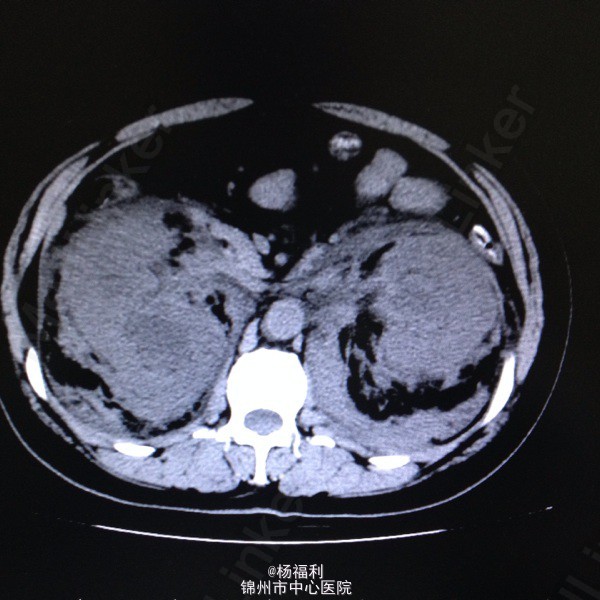

44岁女患。为消化科我会诊患者。 现病史:以上腹痛9小时为主诉入院。无发热及寒战、噁心未呕吐,无腹泻及黑便。 既往史:双眶炎性假瘤2年,口服激素治疗,并补钾。

查体:上腹部压痛,无反跳痛、右侧压痛明显,右肾区叩击痛,左肾区轻叩击痛,双输尿管走形区无压痛。 辅助检查;泌尿系彩超:双肾积水。 血白细胞:9.99*10^9。 肾功能正常。 全腹部ct及MRU检查:见图片。

诊断;真的不知道是啥病。 处理:暂时止痛处理。双肾病变。不知从哪里下手。